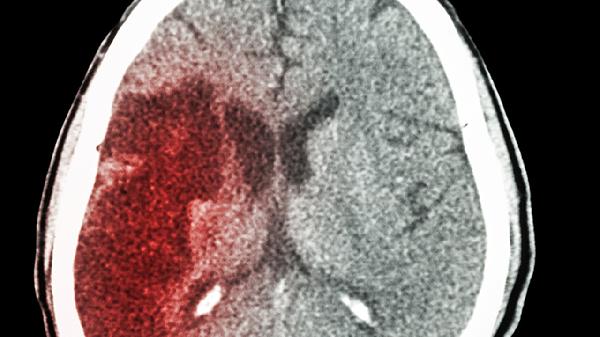

脑出血后脑组织需要时间修复,过早进行体力劳动可能加重脑部负担。出血量较小且未累及关键功能区时,部分患者在1个月后经医生评估可逐步恢复轻体力活动,如散步或简单家务。若出血量稍大或伴有轻微神经功能损伤,通常需2个月左右静养,期间需避免提重物、弯腰等动作。恢复期超过3个月的情况多见于出血位置特殊或合并基础疾病患者,需严格遵循康复计划。康复过程中需定期复查头颅CT,观察血肿吸收情况,同时监测血压、血糖等指标。